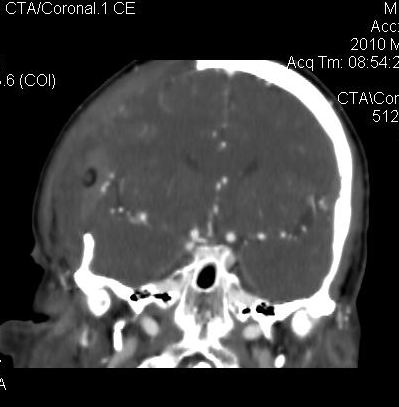

男.60岁,渐进性意识不清,ct检查双侧额颞顶部硬膜下血肿,开颅术后行脑血管cta,大脑中动脉起始部见一瘤状血管扩张。请各位老师留下宝贵意见

太常见了,报动脉瘤就可以

符合动脉瘤表现。

符合动脉瘤表现。

动脉瘤。

颅内动脉瘤。

小动脉瘤

典型

符合动脉瘤的表现

动脉瘤

符合动脉瘤表现。

小动脉瘤

典型